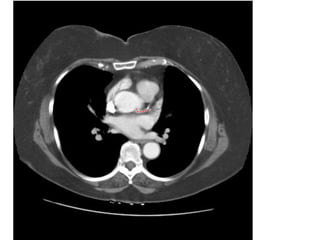

Giải phẩu CT ngực – các mạch máu

lớn.

SVC: tĩnh mạch chủ trên.

Aortic arch: cung đm chủ

Pulmonary artery: đm phổi

Main sterm bronchus: phế quản gốc